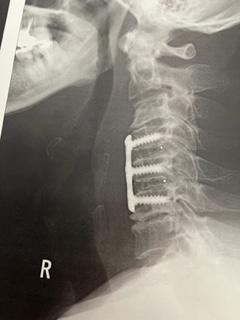

龍香店主のレントゲン!

レントゲンで見えるチタンのプレートです。

ビスが6本で固定してあります。これで

4.5.6番目の頚椎を一つに固めてしまうらしい。

間に人工の椎間板が二枚入っているらしい…

レントゲンでは見えませんが…

これで、問題だった4.5.6番目の頚椎のヘルニアが

進むことはありません。あとは、この右手が元どおり動いてくれる事が一番の問題なんです…

まだ、手術前と変わってないと思います…

変わり出すのがいつになるやら…悲iPhoneから送信